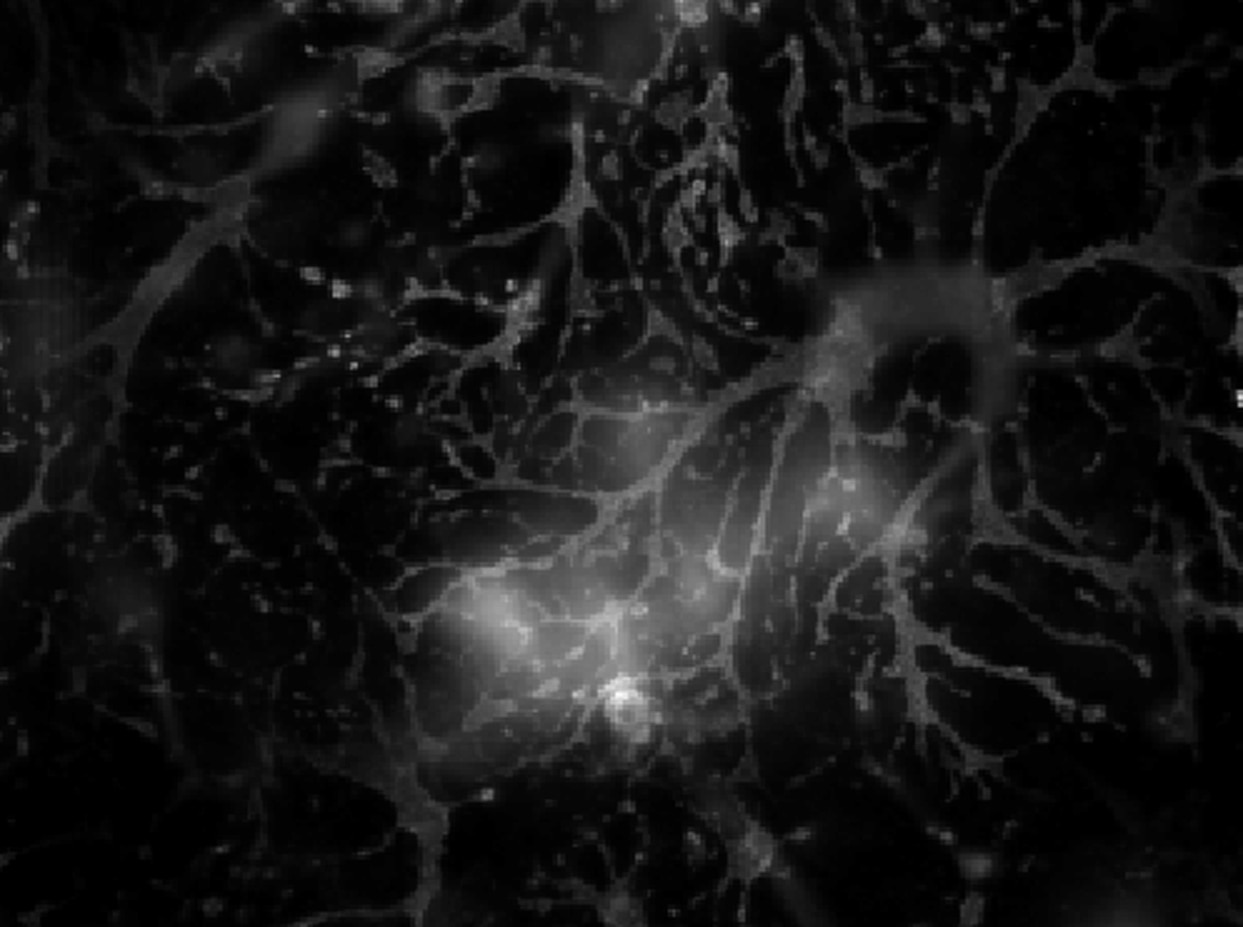

Immunocytochemistry/ Immunofluorescence: Adenosine A2aR Antibody [NB300-597] - Mixed cortical rat neurons culture (21 DIV) stained for A2A labelled with Alexa647. The staining visualised the astrocytes in culture. This ...read more

Immunocytochemistry Adenosine A2aR NB300-597

ICC Rat 06/27/2017

ApplicationImmunocytochemistry

Sample TestedPrimary rat cortical neurons

SpeciesRat

CommentsFixation Solution and Conditions: 4% paraformaldehyde in PBS, 15 minutes RT

Blocking Solution & Duration: 3% BSA in PBS with 0.2% saponin, 30 minutes RT

Primary Antibody Diluent and Dilutions Tested: 1:120 in 1% BSA in PBS with 0.2% saponin, over night 4°C

Secondary Antibody Manufacturer, Host Species, Dilution, & Diluent: Thermo donkey anti-rabbit Alexa647, 1:500 in PBS with 0.2% saponin, 1 hour, RT